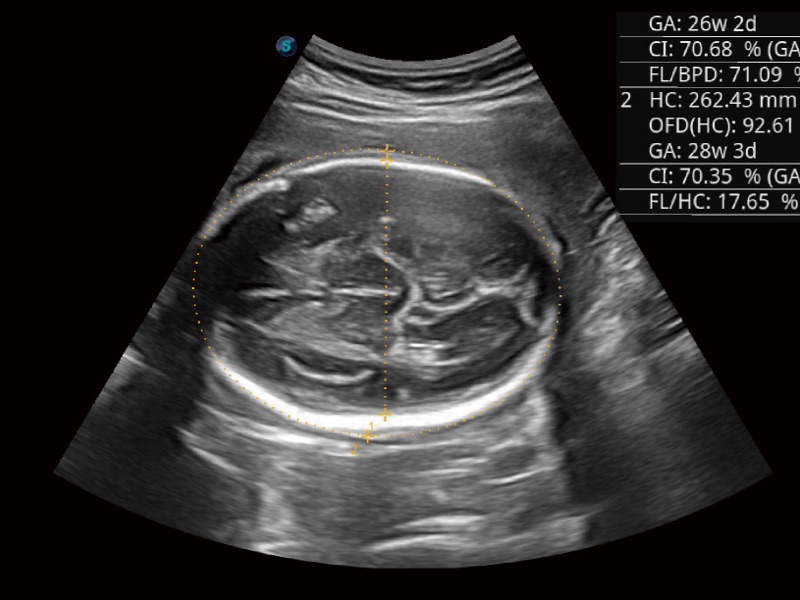

• 妇产科应用

• 光影成像

三维光影成像技术采用新型的渲染方式,增强边缘信息,使得轮显示清晰完整,为临床提供丰富、直观的三维结构,提供临床诊断准确性。